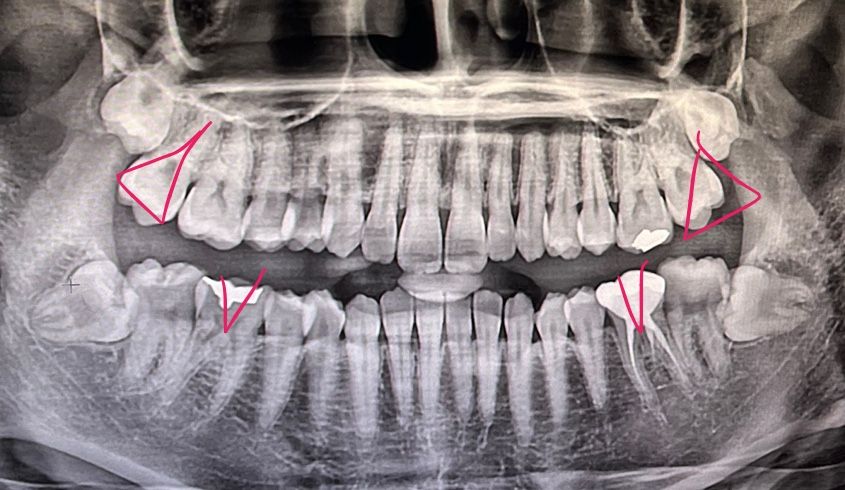

부정교합인 어금니에 세모 표시, 통증이 느껴지는 어금니에 체크 표시를 했습니다.

안녕하세요. 현재 아래쪽 어금니 두 개(사랑니 앞에 앞에 있는)와 턱근육 통증을 느낀지 거의 두 달 가량 된 상태입니다. 턱근육은 약물치료를 받다가 보톡스를 맞은지 3주 정도 된 상태인데 여전히 통증이 있습니다. 아래쪽 어금니 두 개도 통증이 있구요. 저는 아래쪽 매복수평사랑니가 밀어서 아픈 줄 알고 구강악안면외과에 갔는데 매복사랑니 때문이 아니라 위쪽 마지막 어금니들이 부정교합이라서 아래쪽 어금니에 부담이 많이 갈 확률이 높다고 하셨습니다. 그리고 교정을 권유하셨는데 위쪽 어금니 두 개만도 교정이 가능한가요? 교정을 진행하게 된다면 혹시 발치도 해야 할까요?

파노라마상태로는 교합을 확인을 할수가 없습니다. 구강외과 말대로 부정교합때문에 치아가 예민해져서 그런거라면 교정을 하시는게 좋습니다. 부분교정은 어려울껏같고 전체교정을 하셔야될것같습니다. 교정을 하게 되면 사랑니도 발치를 하셔야될것같습니다.